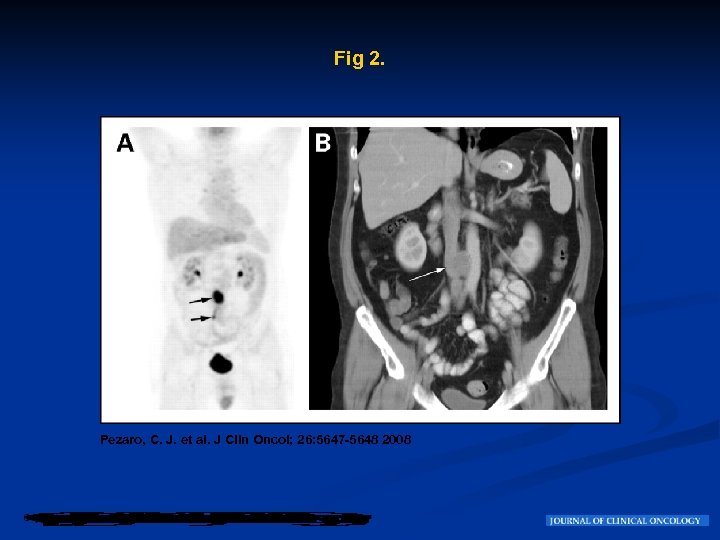

Historia Clínica n n No recibió tratamiento adyuvante pero fue manejado en otro Centro de un programa con un activo control de seguimiento por el lapso de 5 años, con examen físico periódico, marcadores tumorales y Tomografías Computadas (CT) que fueron todas normales , por 5 años luego de la orquiectomía. . En el año 2007, a los 52 años, consulta por antecedentes de 12 -meses de dolor abdominal y de espalda. El examen físico era normal. La BHCG y la alfa feto-proteína sérica dentro de los límites de normalidad. , pero la lactosa dehidrogenasa fue marginalmente elevada : 537 U/L ( rango normal , 230 a 460 U/L). La tomografía Abdominal CT mostró una masa retroperitoneal (Fig 1,

Fig 1. Pezaro, C. J. et al. J Clin Oncol; 26: 5647 -5648 2008

Evolución Esta masa fue biopsiada y mostró NSGCT. n Fue referido a nuestro Centro para su posterior manejo. Se realizó una tomografía por emision de Positrones (FDG-PET) que mostró una avidez a la captación de una masa ganglionar en el nivel de L 3 en los ganglios interaortocavos con una extensión caudal por debajo de la cadena de ganglios (Fig 2 A). Figure 2 B muestra claramente la localización interaortocavo posterior de la masa tumoral. n